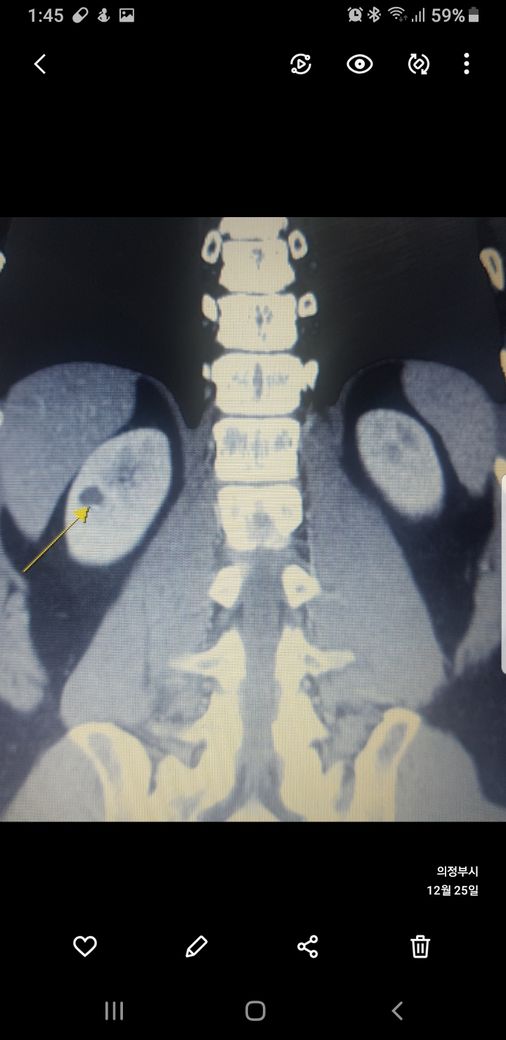

복부ct 작년 11월 , 올해 12월 촬영분입니다.

우측신장에 작년에는 1.7cm 물혹이 올해는 같은곳에 1.2cm 출혈성낭종이라는데

사진 1~4번째 는 작년

둘다 같은 병변이고 비조영증강에서 약간의 고음영 소견이 있어 출혈성 낭종이 의심됩니다.

신장의 낭성병변의 분류에서 1, 2, 2F, 3, 4이렇게 나뉘는데, 2에 해당되는 소견입니다.